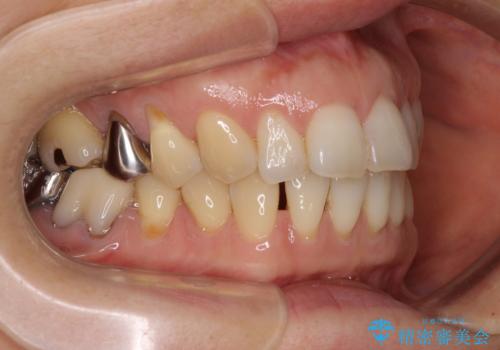

上顎正中が右側にずれていたので、むし歯が酷く抜歯が必要な左側臼歯を抜歯して正中を改善することとしました。

左下には新しいセラミックのブリッジが装着されていたため、ブリッジを壊さずに改善できるところまで咬み合わせを改善していくこととしました。

右上小臼歯は銀歯が装着されており、ワイヤー矯正の装置が装着できないため、事前に仮歯に変えてから矯正治療を行い、その後オールセラミッククラウンにて補綴治療を行いました。